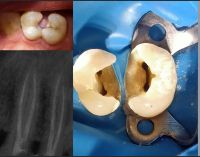

General Dentist with 4 + years of hands - on clinical experience in private and governmental clinics. Skilled in endodontics, restorative dentistry, pediatric cases, and fixed prosthodontics. Known for accurate diagnosis, efficient chairside work, and high patient satisfaction. DHA licensed and available for immediate work